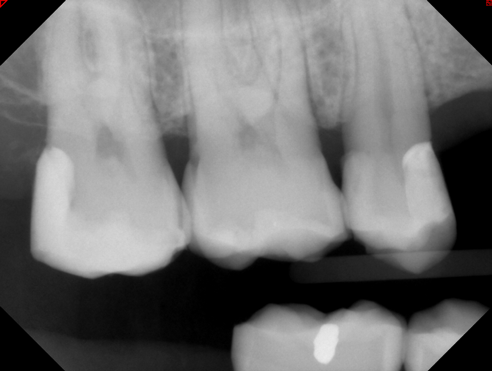

Figure 8A is a radiograph revealing deep root caries previously restored temporarily by a resident at the AEGD Residency Program clinic with glass ionomer utilizing a lateral rather than occlusal approach. After the glass ionomer failed to adhere, another resident again attempted a lateral approach that resulted in the restoration shown in Figure 8B. A third resident had success with an occlusal approach, removing a failed occlusal composite to access the distal  (Figure 9). This attempt was successful both in the preparation of the lesion and in the placement of a dual- cure bulk-fill flowable (Bulk EZ Plus, Zest Dental Solutions; alternatively: HyperFIL®, Parkell; Fill-Up!, Coltene) extruded through a bendable needle (Figure 10). Figure 11 shows the final preparation after tissue removal was accomplished with rotary gingitage; note that this was performed with the rubber dam in place. An air abrasion device (Groman Etchmaster, Groman Dental; alternatively: PrepStart H2O, Zest Dental Solutions; Bioclear Blaster, Bioclear) was used with potassium bicarbonate to remove biofilm prior to acid etching (Figure 12). Phosphoric acid 37% was utilized in a total etch fashion (Fig- ure 13 and Figure 14) for 20 seconds. Figure 15 shows the universal bond (Scotchbond Universal, 3M; alternatively: All-Bond Universal®, BISCO; Prelude One, Danville Materials) with metha- cryloyloxydecyl dihydrogen phosphate (MDP) being scrubbed into the cavity for 20 seconds. After air thinning for 20 seconds, the adhesive was light cured for 40 seconds at 1,200 mw/cm2power density (Figure 16).

Fig 8. A 77-yearold

male patient presented with a distal lesion on tooth No. 2, previously treated with restorations that had failed.

Fig 8A

Fig 8B